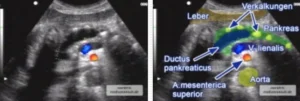

![]() ![]() Sonographischer Oberbauchquerschnitt mit Duplexsonographie der Oberbauchgefäße: Chronisch kalzifizierte Pankreatitis mit starker Erweiterung des Hauptgangs (Ductus pancreaticus). Eine solche Erweiterung gilt als beweisend für eine chronische Bauchspeicheldrüsenentzündung. Sie führt zu einer Retraktion von Pankreasgewebe und damit zu einer Gangerweiterung. Das eingeblendete duplexsonographische Bild zeigt, dass das darunter gelegene Gefäß Blutfluss enthält und die Milzvene (blau) darstellt. Das quer getroffene Gefäß (rot) darunter ist die Arterie coeliaca. |